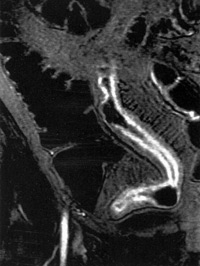

Η μαγνητική εντερόκλυση είναι μία πολλά υποσχόμενη μέθοδος για την απεικόνιση

των παθήσεων του λεπτού εντέρου. Από τη μέχρι τώρα κλινική εμπειρία προκύπτει

η μεγάλη διαγνωστική της αξία στη νόσο του Crohn, τα νεοπλάσματα του λεπτού

εντέρου και στην εντερική απόφραξη. Η μέθοδος είναι χρήσιμη για την παρακολούθηση

ασθενών με νόσο Crohn, απεικονίζει με εξαιρετική ευκρίνεια σημεία απόφραξης

και αποτυπώνει μικρά συρίγγια ή συριγγώδεις πόρους που δεν μπορούν να ανιχνευθούν

με ακρίβεια στη συμβατική εντερόκλυση (εικόνα 9).

ΕIKONA 9. Απεικόνιση εντερικού συριγγίου με α: συμβατική εντερόκλυση, β: μαγνητική

εντερόκλυση.